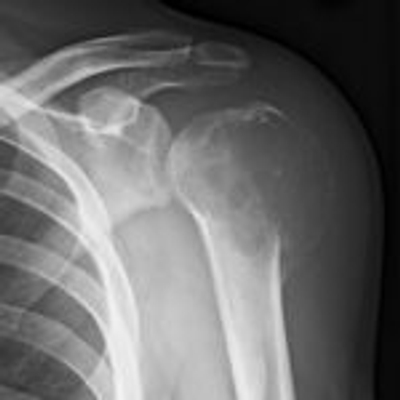

Click on an image below to view more info.